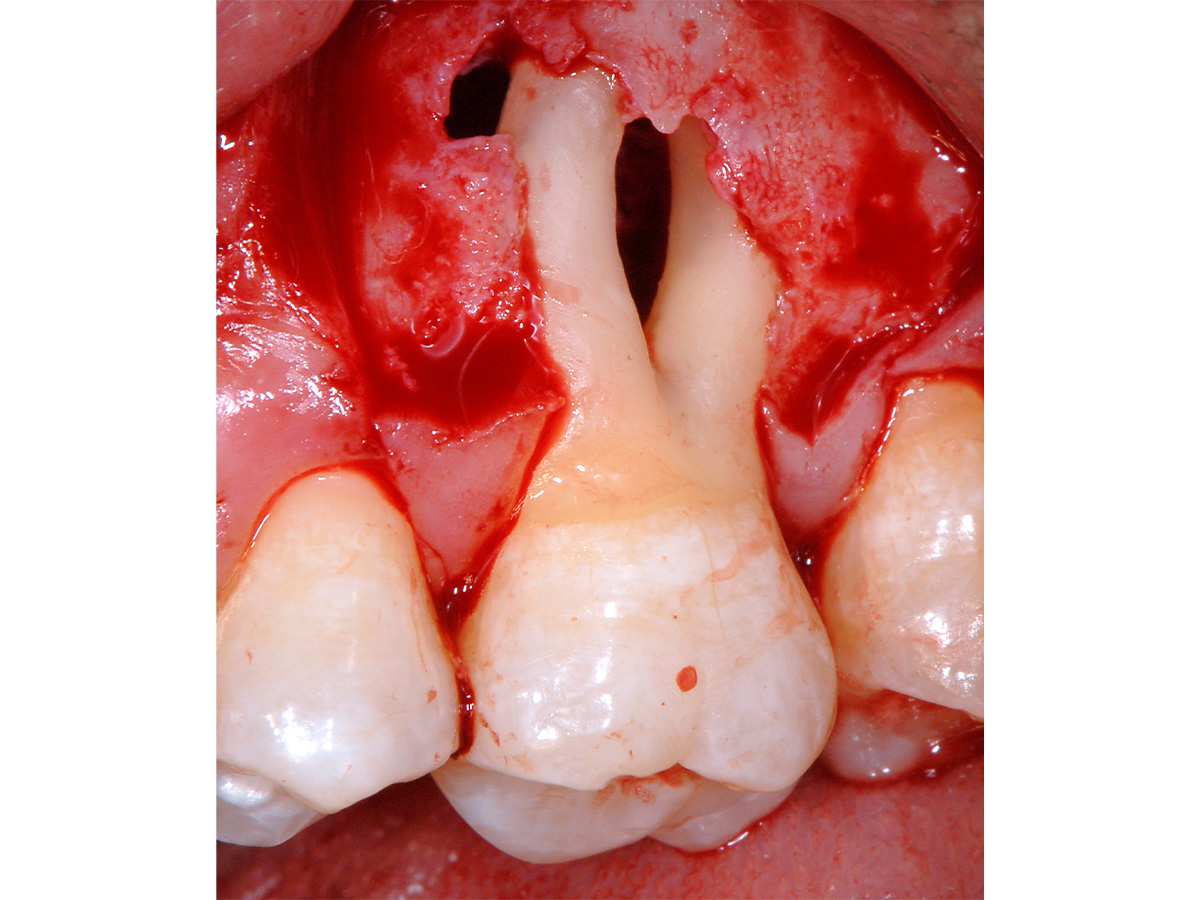

Abbildung 1

Klinische Ausgangssituation: Ausgedehnter parodontaler Furkationsdefekt an Zahn 26 in Kombination mit marginaler Gingivarezession.